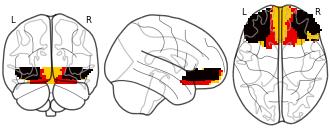

Connectivity-Based Parcellation of the Human Orbitofrontal Cortex: K=3...

EmailClick to copy linkLink copied Cite(2024). Connectivity-Based Parcellation of the Human Orbitofrontal Cortex: K=3 cluster map [Dataset]. http://identifiers.org/neurovault.image:887624niftiAvailable download formatsUnique identifierhttps://identifiers.org/neurovault.image:887624Dataset updatedNov 18, 2024License

Cite(2024). Connectivity-Based Parcellation of the Human Orbitofrontal Cortex: K=3 cluster map [Dataset]. http://identifiers.org/neurovault.image:887624niftiAvailable download formatsUnique identifierhttps://identifiers.org/neurovault.image:887624Dataset updatedNov 18, 2024LicenseCC0 1.0 Universal Public Domain Dedicationhttps://creativecommons.org/publicdomain/zero/1.0/

License information was derived automaticallyDescriptionK=3 cluster map based on N=13 participants.

Collection description

K-means cluster maps of orbitofrontal cortex with K=2, 3, 4, 5, 6, and 7 clusters based on resting-state fMRI data.